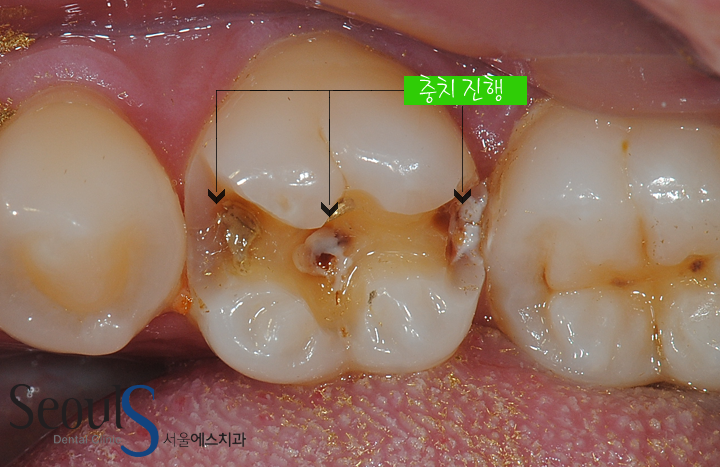

골드인레이 어금니 충치치료

금으로 때웠던 치아에 충치가 진행되고 있습니다

금니 주변을 보시면 치아 표면이 검게 보이는 부분이 있습니다

치아 속으로 충치가 진행되면

진행되고 있는 충치가 비춰 보여 치아 표면이 검게 보입니다

그리고 치아의 오른쪽 끝을 보시면 치아속으로 충치가 진행되고 있습니다